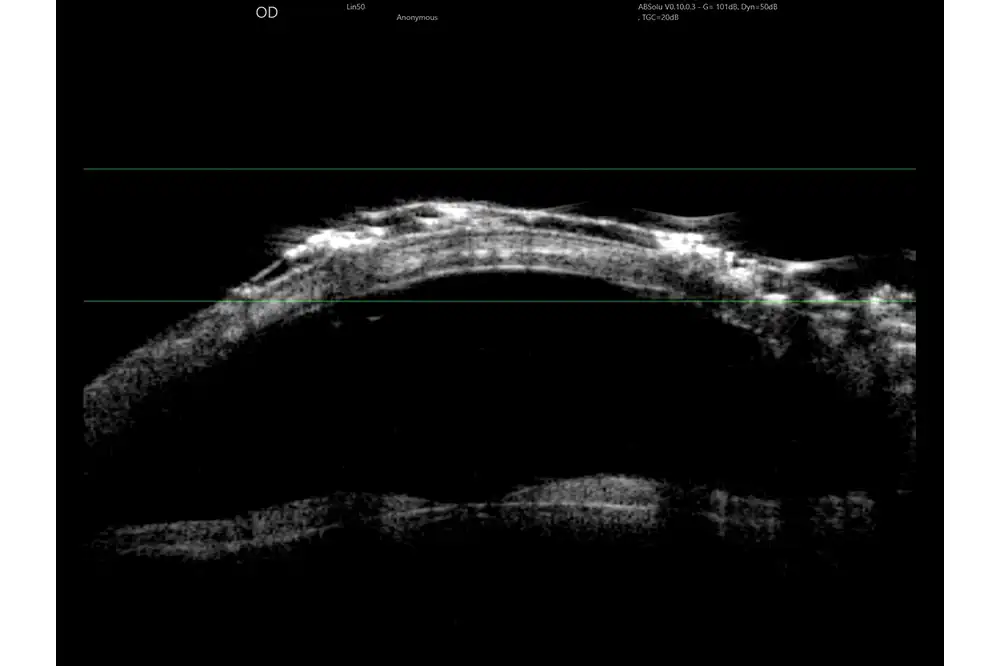

Quantel Medical heeft een sprong voorwaarts gemaakt met de nieuwe technologie met 5 ringen op een 20 MHz-sonde. Het principe is om om en om ultrasone geluidsgolven uit te zenden via 5 concentrische transducers in dezelfde sonde. Deze technologie:

- Verhoogt het focusgebied

- Vermindert de laterale resolutie van 250 naar 200 µm, oftewel met 25%

- Behoudt een hoge axiale resolutie

Het volledige oog is nu zichtbaar met een uitstekend detailniveau.